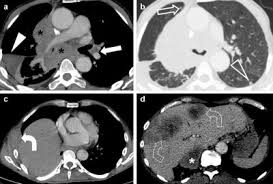

El estudio preclínico realizado con ratones ha confirmado que al inhibir esta proteína no solo se impide el crecimiento de los tumores de mama más comunes y de la metástasis de pulmón, sino también de los dos tipos de cáncer de pecho más agresivos: el Her2 y los triples negativos, los subtipos más difíciles de tratar debido a su alta malignidad.

Sin embargo, aunque el diagnóstico y el tratamiento de esta enfermedad han mejorado, este tumor sigue siendo el que más muertes registra (6.300 fallecidas en 2011), debido, principalmente, al desarrollo de resistencias a los tratamientos actuales y, sobre todo, al desarrollo de metástasis que dificultan el tratamiento de las pacientes.